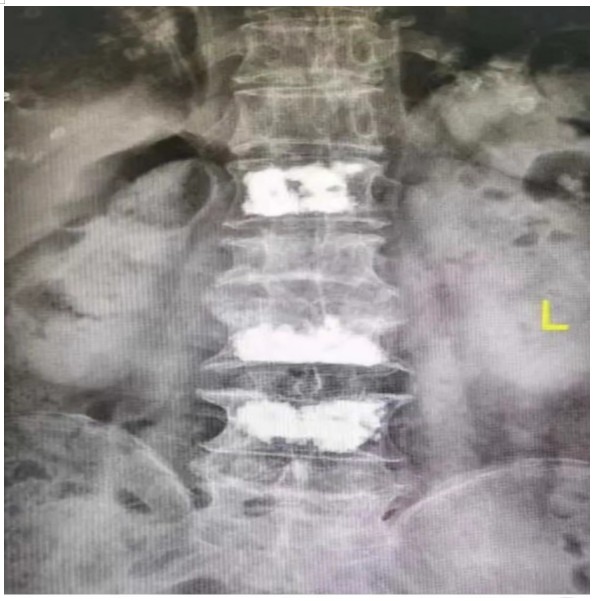

原來,89歲的占大爺因在家勞作時突發(fā)腰背部疼痛難忍、腰部無法直立,行走困難,在家臥床休息兩周后疼痛仍未減輕,于是來到衡陽市中心醫(yī)院脊柱外科就診。接診的盛凱醫(yī)師仔細(xì)查體結(jié)合磁共振檢查發(fā)現(xiàn),占大爺腰椎L1、L3、L4有椎體壓縮骨折,診斷為腰椎體壓縮骨折、重度骨質(zhì)疏松癥。錢軍博士團(tuán)隊結(jié)合對病人多椎體的骨折做出了細(xì)致的評估,經(jīng)過認(rèn)真分析研究,決定為患者實施腰椎體壓縮性骨折經(jīng)皮穿刺椎體成形術(shù)(PVP)。手術(shù)當(dāng)天,醫(yī)師團(tuán)隊在C-臂監(jiān)視器透視下,分別定位L1、L3、L4雙側(cè)椎弓根位置,以標(biāo)記穿刺點(diǎn)為中心做3mm切開,在透視下注入骨水泥,再次透視見骨水泥位置良好,順利完成手術(shù)。

據(jù)悉,該手術(shù)經(jīng)皮透視下穿刺,手術(shù)切口小,創(chuàng)傷小,無需縫合,微創(chuàng)手術(shù)皮膚切口僅2-3毫米,僅僅一個穿刺針的長度,通過穿刺針注入骨水泥,骨水泥可以達(dá)到穩(wěn)定椎體骨折、恢復(fù)椎體力學(xué)強(qiáng)度、防止椎體進(jìn)一步壓縮和緩解疼痛的目標(biāo),使患者早期恢復(fù)正常活動。優(yōu)點(diǎn)為創(chuàng)傷小,臥床時間短,花費(fèi)少。對于老年人椎體骨折微創(chuàng)下椎體成形術(shù)為最適宜該患者的治療方法。術(shù)后患者即感腰部疼痛明顯減輕,第二天可下床行走,已無腰痛不適,如此快速地恢復(fù)讓患者占大爺非常高興,自己再也不會受腰痛折磨整日與床為伴了,當(dāng)即給脊柱外科團(tuán)隊送上了錦旗表示感謝。